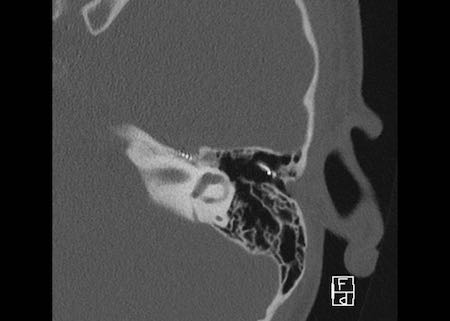

Bên trái là hình ảnh của một bé gái 2 tuổi.

Các hình ảnh từ kết quả chụp CT được thực hiện trước khi cấy ốc tai điện tử.

Quan sát thấy dị dạng nhẹ ở đỉnh ốc tai – không có sự phân tách giữa vòng thứ hai và vòng thứ ba, và trụ ốc tai xương vắng mặt.

Cống tiền đình bình thường.